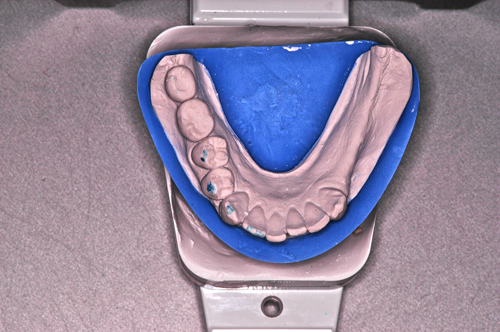

Palabras Clave: ELG: Estereolitográfico OH: Oclusión Habitual ORC: Oclusión en Relación Céntrica Paciente de 35 años de edad ,sexo masculino que lo derivan para implantar el tercer cuadrante. A la auscultación presenta ruidos articulares de tipo chasquido que remiten temporalmente luego de limitación de apertura bucal y maniobras quinesiológicas distractoras. También se observan recidivas de caries en algunos empastes y falta de disclusión canina de ambos lados. Se estudia el caso desde un punto de vista clínico, scanografico mediante Dentascan y tridimensional mediante montaje en articulador. A partir del scanner se obtienen datos para confeccionar modelo estereolitográfico (ELG),operar en el y construir férula quirúrgica dento-muco soportada. Habitualmente se procede directamente a implantar, dado que ese era el requerimiento del profesional derivante y el deseo del enfermo. Sin embargo, esa actitud enmascararía otro tipo de problemas que la boca presenta. Se consulta al odontólogo derivante, y coincide con mi opinión acerca de que si solo se lo implanta, sin corregir la posición mandibular, la situación de las ATMs, los empastes sin anatomía y la falta de disclusiones, el resultado final no será el deseado y su eficacia masticatoria no funcionará optimamente. Consultado el paciente coincide y acepta ese concepto y entonces procedemos a confeccionar un Jig de Lucia a partir del montaje de estudio, y lo dejamos puesto en boca toda la noche anterior a la consulta, para proceder a realizar un ajuste oclusal al día siguiente sin engramas anteriores, lo que facilita no tener que relajar nuevamente con laminillas de Long. En esta etapa pierde el implante correspondiente a la pieza 4.7 que traía en boca. Estabilizado el sistema, procedemos a la parte quirúrgica, comenzando por instalar la férula, retirar opérculos gingivales mediante bisturí circular, fresado óseo e instalación de implantes ,toma de impresión a cubeta fenestrada (pegando con metacrilato sin cambios dimensionales, los transfers a la cubeta especialmente diseñada.(1º método de pasividad protética utilizado), e instalación de tornillos de cicatrización. Inmediatamente de retirada la cubeta de boca y colocadas las réplicas de los implantes, procedemos a ferulizar los “ápices” de las réplicas para que no sufran movimientos durante el llenado de la impresión.(2º método de pasividad protética utilizado). Controlamos radiograficamente Tres meses después, procedemos a tomar nuevos registros de arco facial, registros intermaxilares en Oclusión en Relación céntrica, montaje de los modelos obtenidos intra operatoriamente y confección de un conjunto de cuatro coronas provisionales de metacrilato en el sector implantado y las correspondientes al maxilar superior. Verificada la perfecta función de todos los componentes, ausencia de todo tipo de síntoma y comprobada la paz en todo el sistema, procedemos tiempo después a confeccionar las fundas definitivas, que constituyen el “cerrojo” de la dinámica del mismo. Por último, corroboramos la oclusión fundamentalmente en lo que hace a la:

Se observan depósitos de sarro incluso en oclusal

La anatomía de las piezas protéticas no responden a la función